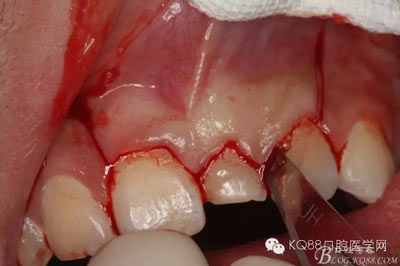

圖4.腭側(cè)觀:左乳Ⅰ腭側(cè)牙齦正常,無松動,擬摘除牙瘤,暫時保留左乳Ⅰ。